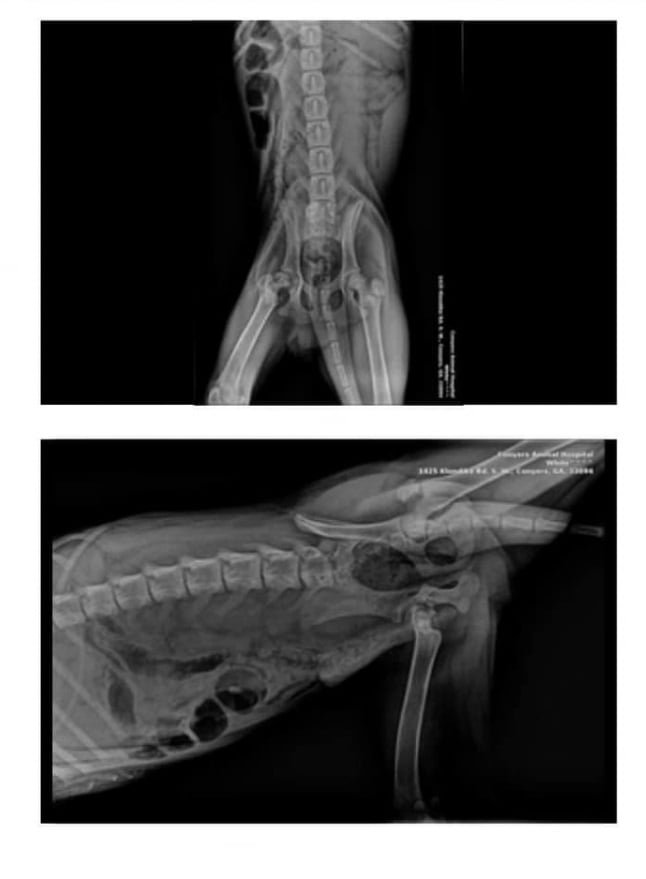

Hank’s physical condition was grave.

The veterinary team found that his leg had been broken for over two weeks, a painful reality that explained his unwillingness to leave the comfort of his bed.

Immediate medical attention was necessary, and Hank was on the verge of being euthanized due to the severity of his condition.